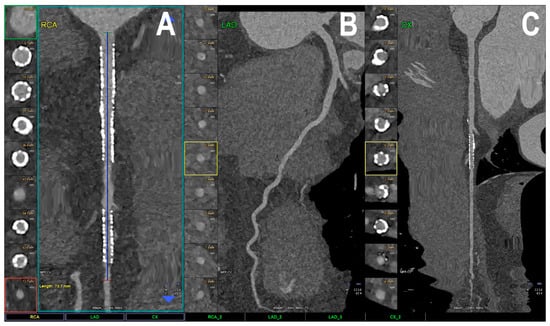

- Han, D.; Liu, J.; Sun, Z.; Cui, Y.; He, Y.; Yang, Z. Deep learning analysis in coronary computed tomographic angiography imaging for the assessment of patients with coronary artery stenosis. Comput. Methods Programs. Biomed. 2020, 196, 105651. [Google Scholar] [CrossRef]

- Lin, A.; Manral, N.; McElhinney, P.; Killekar, A.; Matsumoto, H.; Kwiecinski, J.; Pieszko, K.; Razipour, A.; Grodecki, K.; Park, C.; et al. Deep learning-enabled coronary CT angiography for plaque and stenosis quantification and cardiac risk prediction: An international multicentre study. Lancet 2022, 4, e256–e265. [Google Scholar] [CrossRef]

- Zreik, M.; van Hamersvelt, R.W.; Wolterink, J.M.; Leiner, T.; Viergever, M.A.; Isgum, I. A Recurrent CNN for Automatic Detection and Classification of Coronary Artery Plaque and Stenosis in Coronary CT Angiography. IEEE. Trans. Med. Imaging 2019, 38, 1588–1598. [Google Scholar] [CrossRef]

- Choi, A.D.; Marques, H.; Kumar, V.; Griffin, W.F.; Rahban, H.; Karlsberg, R.P.; Zeman, R.K.; Katz, R.J.; Earls, J.P. CT Evaluation by Artificial Intelligence for Atherosclerosis, Stenosis and Vascular Morphology (CLARIFY): A Multi-center, international study. J. Cardiovasc. Comput. Tomogr. 2021, 15, 470–476. [Google Scholar] [CrossRef]